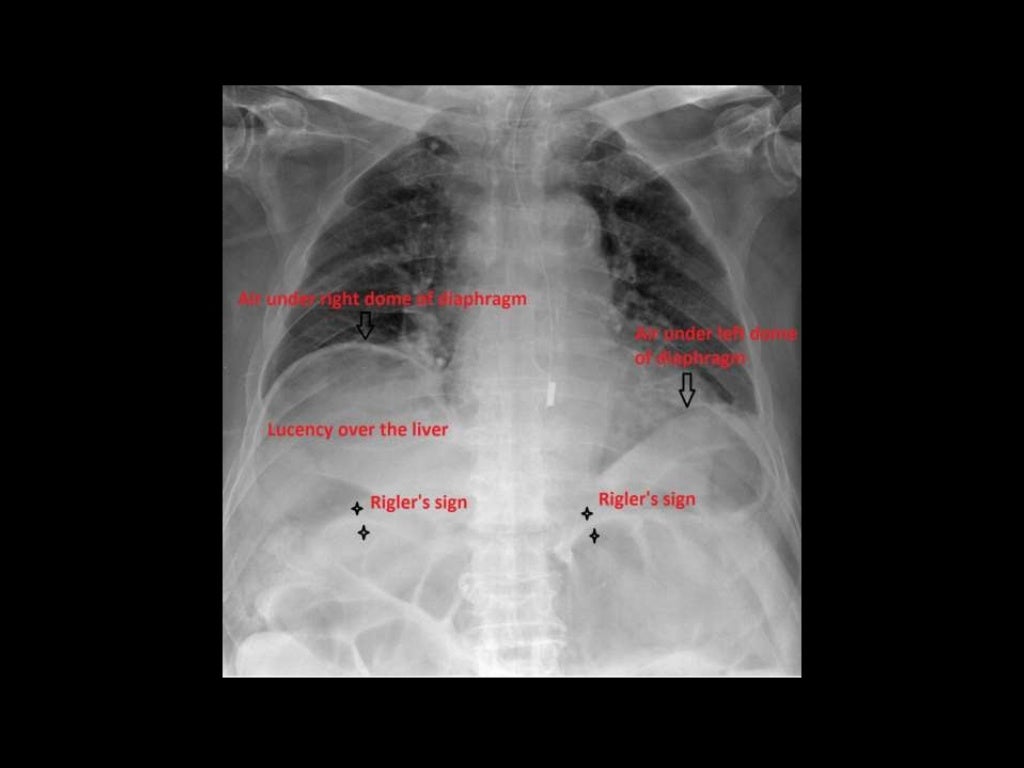

Figure 1 from Pneumoperitoneum on Supine Abdominal XRay Case Report Frozen Abdomen Radiology We report our experience with a patient who presented with frozen abdomen after wound dehiscence due to surgical site infection and. The main aims of imaging in cases of suspected bowel obstruction are: Sonography and ct enable an accurate and rapid triage of patients with an acute abdomen. Differentiate true mechanical obstruction from ileus or constipation. When evaluating the abdomen. Frozen Abdomen Radiology.